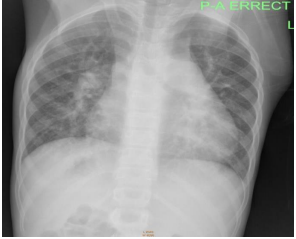

Chest x-ray showed prominent central pulmonary vessels, increased pulmonary lung markings, and an enlarged heart narrowed superiorly (string-on-egg sign) (Figure 3).

Figure3: Chest x-ray showingincreased pulmonary vasculature with marked cardiomegaly.